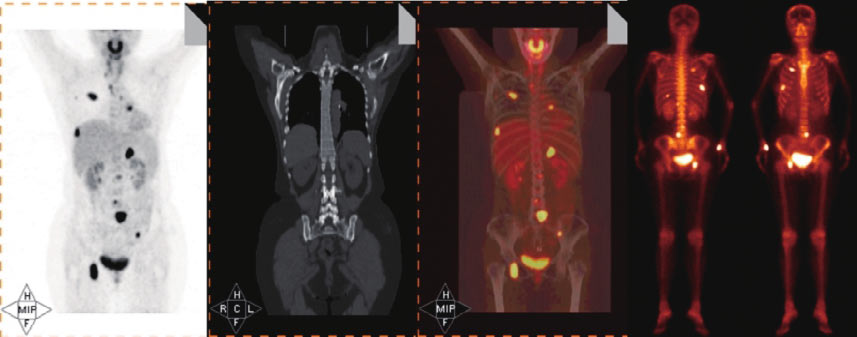

规培朋友看过来--核医学病例及解析(183号)

1010x864 - 275KB - PNG

规培朋友看过来--核医学病例及解析(183号)

531x635 - 130KB - PNG